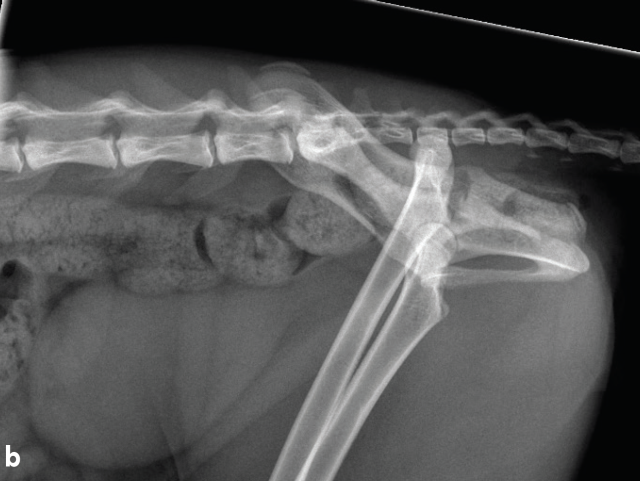

Comparison of complications and outcomes of cats with hip luxation treated with toggle rod technique using either ultrahigh-molecular-weight-polyethylene or nylon: a multi-institutional retrospective study

Coxofemoral luxation is frequently encountered in feline orthopaedic practice and is the commonest luxation in this species. A variety of surgical techniques have been described, with re-luxation rates ranging from 10-33%.1-4 Few studies have reported the use of toggle rod stabilisation for feline coxofemoral luxation.2,5,6 Very-good-to-excellent long-term outcomes were reported for 11 of 14 cats and a re-luxation rate of 14% in a study using polydioxanone.2 Excellent short-term outcomes were described for four cats using ultrahigh molecular weight polyethylene (UHMWPE).5 There are no large studies reporting use of UHMWPE or nylon for toggle rod stabilisation of hip luxation in cats, or studies that compare complications and outcomes of cats managed with UHMWPE or nylon.

The objectives of the study led by Dr Mullins are to describe the rate and type of intraoperative and postoperative complications and outcomes of toggle rod technique in cats, to compare the rate of complications and outcomes of cats treated with UHMWPE or nylon, and to identify risk factors for development of complications and non-excellent outcome. This will be a multi-institutional study involving ten referral centers. Outcome will be assessed based on the results of a designated telephone owner questionnaire.